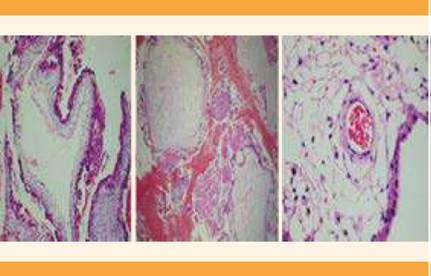

El estudio histopatológico reportó: partes fetales, eritrocitos nucleados en los capilares de las vellosidades y vellosidades hidrópicas con hiperplasia trofoblástica (Figura 4); se confirmó el diagnóstico definitivo de mola hidatiforme completa y feto vivo coexistente, derivado de un embarazo gemelar bicorial biamniótico.

Figura 4 En el lado izquierdo y en medio se muestran las vellosidades hidrópicas con hiperplasia trofoblástica características de la mola hidatiforme completa. En el lado derecho se muestran eritrocitos nucleados, característicos del embarazo normal con feto vivo o mola parcial.

El examen histopatológico de la placenta es indispensable para descartar un posible coriocarcinoma. Los reportes al respecto fueron (Figura 4) hallazgos característicos de embarazo gemelar, con dos placentas, en donde una tenía vellosidades hidrópicas con ausencia de feto y la otra, tejido placentario con eritrocitos nucleados que significaban placentación.